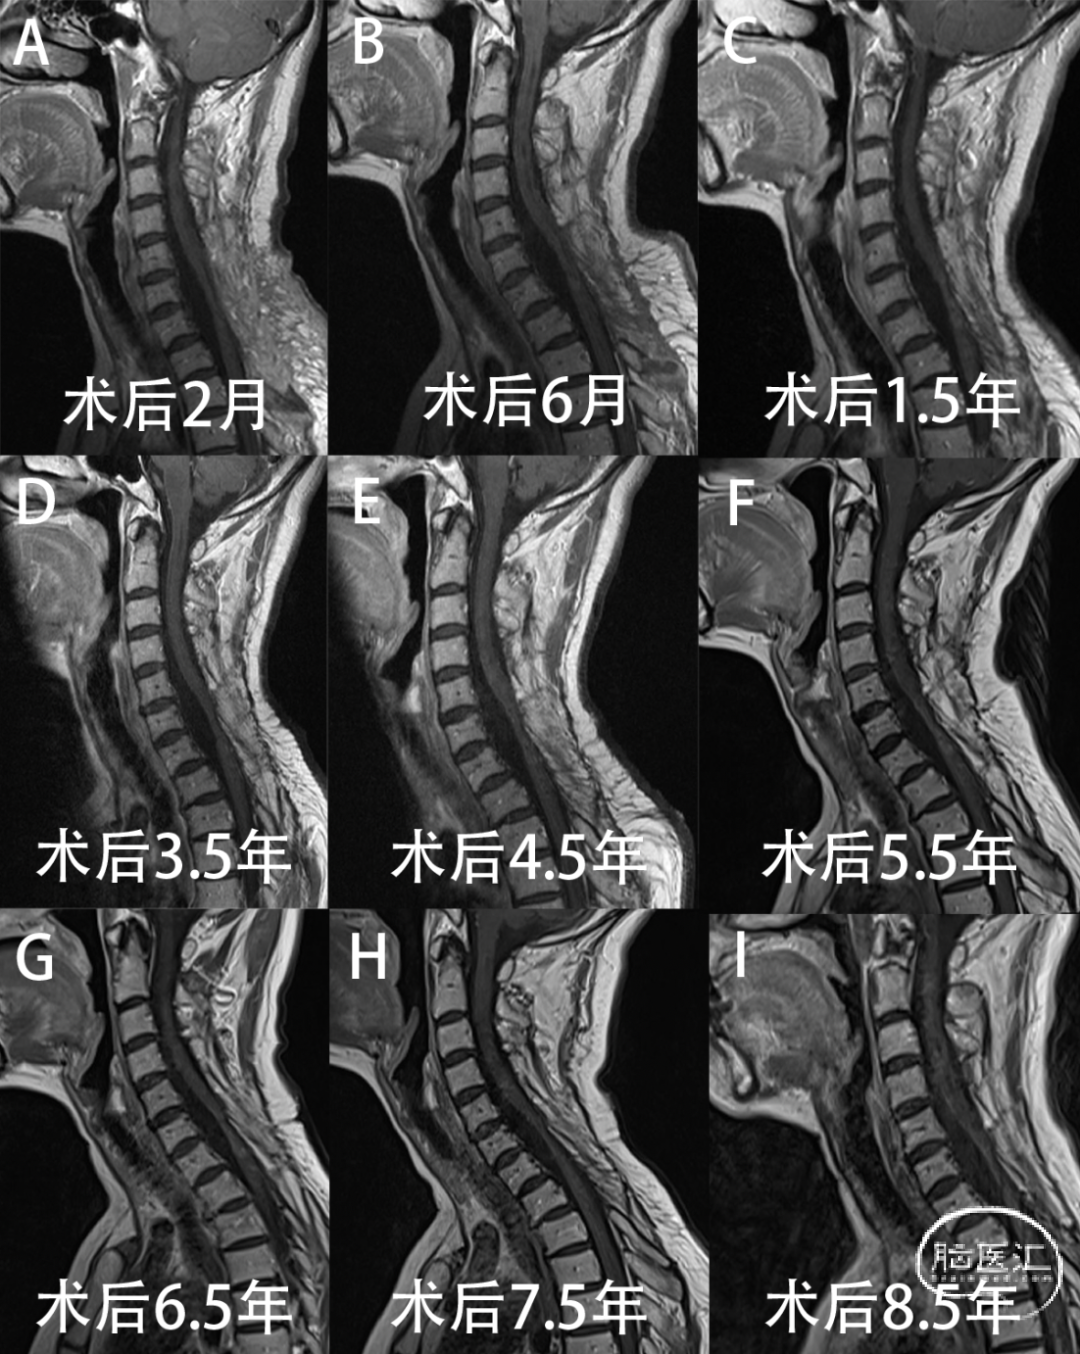

图6. 术后随访增强MRI提示未见肿瘤复发。